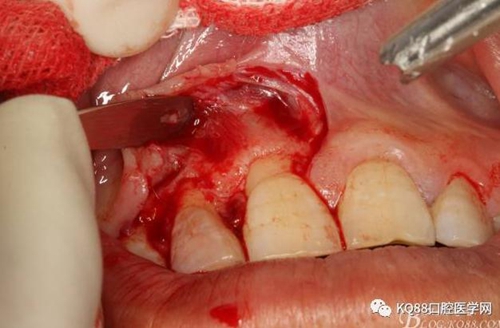

圖8.從垂直切口和水平切口的連接處翻瓣。發(fā)現(xiàn)11和12之間的骨壁有缺損。

圖9.翻開角形瓣后,有骨壁缺損,囊壁有穿孔,這就是溢膿的竇道出口。